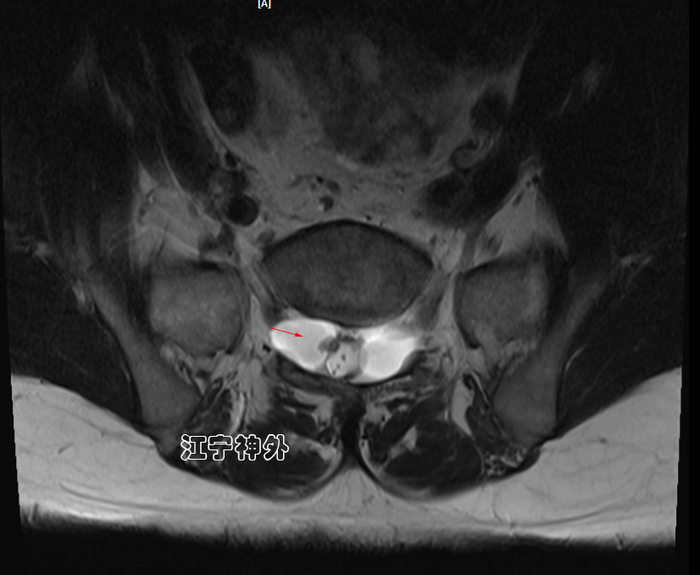

郑主任仔细阅片发现,右侧骶管囊肿虽然比较小,但是其脑脊液漏口处(囊颈)存在一块灰色异常信号,推测可能存在神经根内疝。

正如术前所预计的一样,我们果然发现右侧骶管囊肿的漏口很大,除了本来的穿行神经根,还有两根过路的神经根呈M形疝入漏口,并且与漏口粘连严重,形成嵌顿,这也就解释了为什么右侧骶管囊肿比较小,症状却很严重。

郑学胜主任指出,骶管囊肿本质上不是一个囊肿,而是脑脊液漏;当漏口很大的情况下,脑脊液进出的流速快,就可能将周边过路的神经根带入囊肿,形成神经根内疝,如果疝入的神经根太多,挤压在漏口处,形成嵌顿粘连,症状就会明显加重,这个原理和普外科的疝气是相似的,这种情况应及时手术解决,否则神经根可能严重损伤甚至坏死。